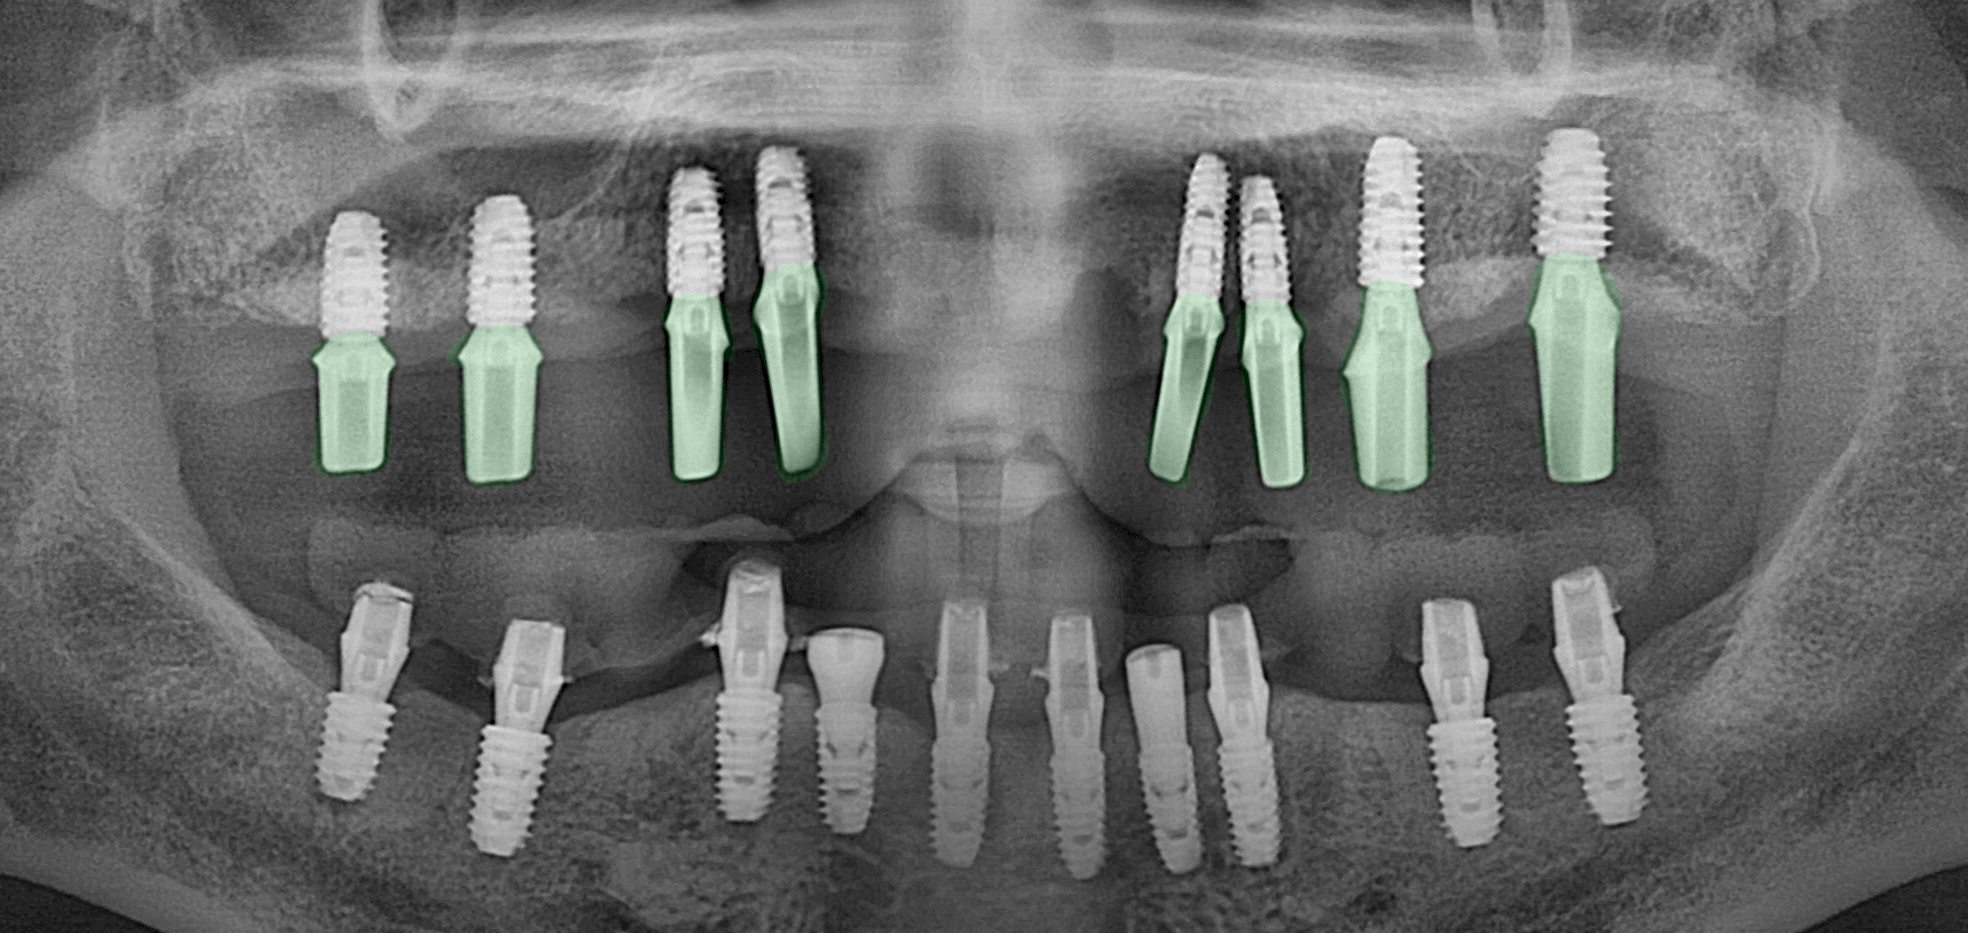

윗쪽에는 8개의 나사를 심고

아래쪽에는 10개의 픽스처를

식립하는 Plan 입니다.

이 과정에서 흡수된 치조골의 양이

너무 많아 골유도재생술(GBR)

즉 뼈이식을 함께 하기로 했습니다.

컴퓨터 분석 시뮬레이션을 바탕으로

식립이 알맞게 진행되었습니다.

2024.09.20

상악은 기성 어버트먼트를

장착하였으며

하악은 임시 치아를

제작하여 체결했습니다.